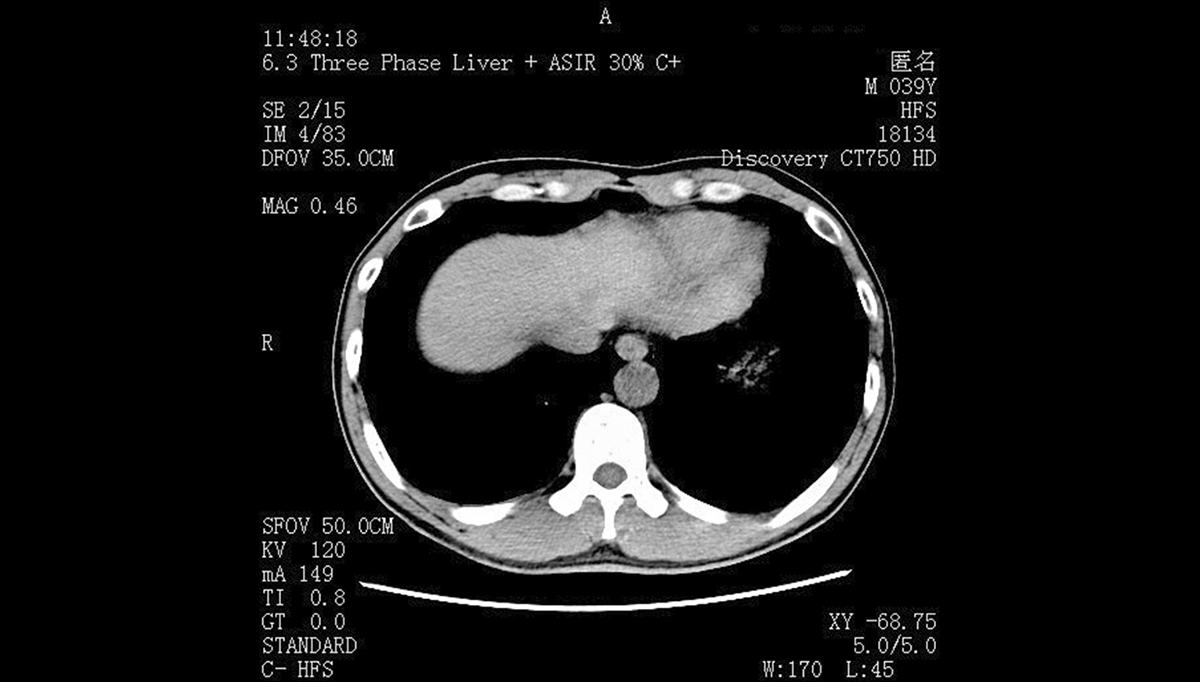

其次,影像显示性能的差异直接影响诊断精度。远程会诊依赖细微的影像细节判断病情,医用显示器的灰度等级可达 10-bit甚至 12-bit以上,能清晰区分肿瘤与正常组织的密度差异;分辨率适配医疗场景,2MP、3MP、5MP 机型分别对应超声、X 光、CT/MRI 等不同影像需求,且亮度恒定在 500-1000cd/m²,适配远程会诊中不同光照环境的阅片需求。反观普通显示器,8-bit 灰度、200-300cd/m² 亮度的参数,极易导致远程传输后的影像细节丢失。